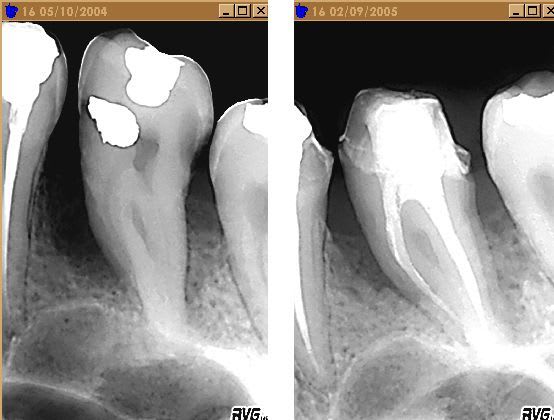

Je remonte ce post de l'oubli pour faire le suivit de cas ( voir premier post, page 1 ).

A noter que l'ODF, finalement, je le fait par activateur SB , donc, pas d'extraction de 15 25 !

Il y a eu tout l'arsenal de la paro med, + laser en juillet., ce n'est pas encore top, mais j'ai bon espoir.

Ce cas remonte à octobre 2004, depuis le microscope m'a permis de voir s'il y avait perte osseuse uniquement sur la 16, je trouvais aussi des maibe au niveau de 26. Donc : traitement complet.

Oups : la radio :